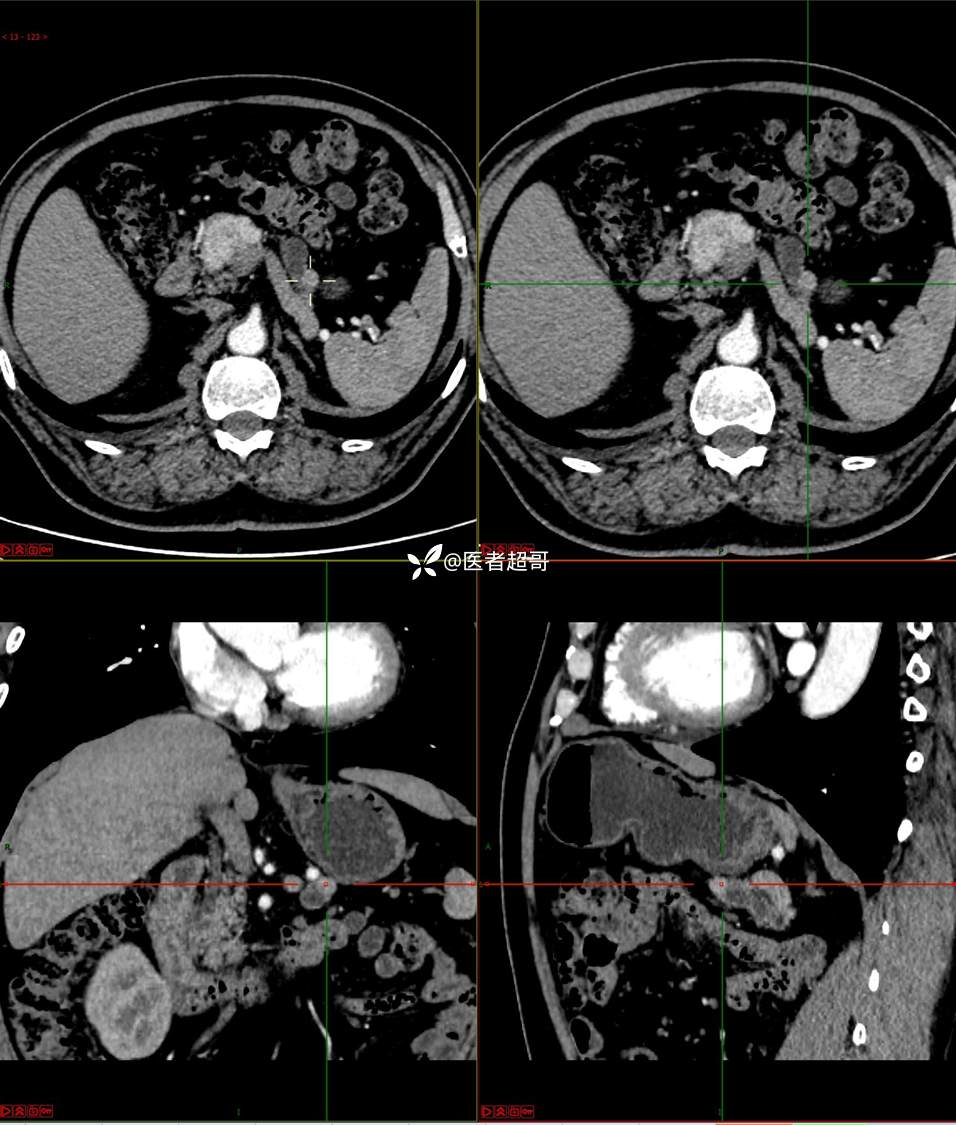

【影诊笔记677】查体发现胰腺占位性病变1周,细节决定成败,请诊断分析!

主 诉:查体发现胰腺占位性病变1周。

现病史:患者1周前在当地查体时发现胰腺占位性病变,无恶心、呕吐,无腹痛,无寒战、高热,无咳嗽、咳痰等异常不适,来我院门诊查上腹部CT平扫+强化:胰腺尾部异常密度灶。今为求进一步治疗,门诊以“胰腺占位性病变”收入院。患者自发病以来,一般情况可,神志清,精神可,普通饮食,二便正常,体重及体力无明显改变。